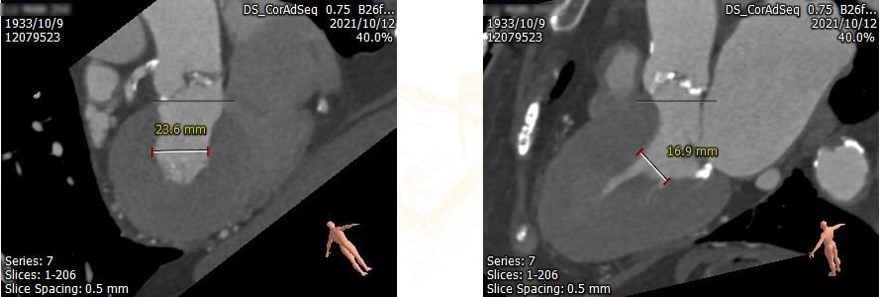

该患者术前CT分析为三叶式主动脉瓣,小瓣环,钙化不重,窦部空间较小,经过团队综合评估后,选用23号二代可回收的TaurusElite瓣膜,局麻下TAVR操作顺利,1个小时完成全部操作,术后患者安返病房。

CT评估:三叶瓣,小瓣环,窦部较小,钙化不重,左室心腔小,冠脉高度可,双下肢入路可。

3、心室大小评估

瓣膜选择:植入23mm TaurusElite瓣膜

本例患者为88岁高龄,外科开胸换瓣手术风险大,患者及家属希望尝试微创介入瓣膜置换。该患者主动脉根部术前CT评估提示瓣环较小,钙化较轻,窦部空间不大,左室心腔小,双下肢入路状态良好。为此我们选择最小型号23二代可回收TaurusElite瓣膜,采取经右股动脉极简式TAVR策略,不全麻、不插管、无导尿、无食道超声。经过吴永健团队熟练配合,瓣膜位置合适,无明显瓣周漏,达到预期效果,患者术恢复良好。